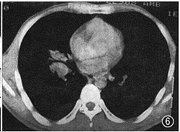

图5 肺窗:右肺门部不规则高密度肿块,大小28 mm×40 mm,CT值68.7 HU,病灶前方邻近外侧隐约见少许散在小点状高密度灶

图6为图5纵隔窗:右中叶支气管壁增厚,管腔略窄

图7 为图5纵隔窗:分歧下淋巴结肿大,短径为20 cm。术前诊断:右侧中央型肺癌,纵隔淋巴结转移;术后病理诊断:干酪增殖性肺结核

图1 肺窗:右肺下叶背段胸膜下孤立结节,直径2 cm,边缘毛糙,CT值54 HU,病灶与胸膜间见多条线影

图2 为图1纵隔窗:病灶密度均匀,边缘光滑。术前诊断:周围型肺癌;术后病理诊断:干酪增殖性肺结核

3.肺门及纵隔淋巴结增大:2例(图5~7),1例表现为血管前、左侧主动脉弓旁支气管分歧下及左肺门淋巴结均增大,并融合成巨块状。另1例表现为右肺门及支气管分歧下淋巴结增大,尤以右肺门淋巴结增大为明显。这2例中1例 22岁,另1例 66岁。